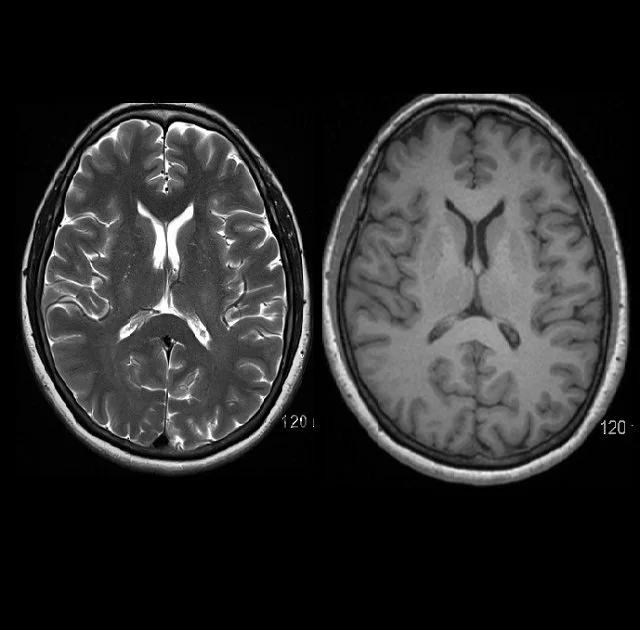

Image T2 (à gauche) et T1 (à droite)

Les images en IRM structurelle sont générées grâce aux propriétés magnétiques qui varient selon les tissus biologiques du cerveau lorsque l’aimant de l’IRM est activé. Il est possible d’obtenir deux types d’images, soit avec un contraste T1 ou T2. Ces paramètres font référence à des dynamiques différentes des protons d’hydrogène des tissus du cerveau. En bref, on peut observer des images dites pondérées en T1, et pondérées en T2. Elles peuvent ressembler à une image inversée l’une de l’autre, mais des distinctions importantes peuvent être faites entre elles. C’est pourquoi on dit plutôt qu’elles sont complémentaires.